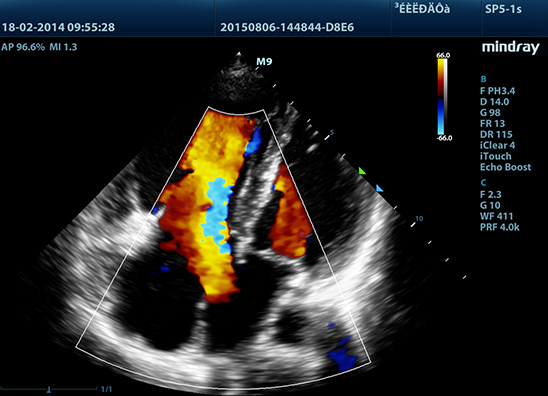

Mindray M9 je dopplerovský ultra ľahký prenosný UZV prístroj najvyššej High End triedy s použitím single crystal 3T sond (vynikajúce zobrazenie blízkeho i vzdialeného poľa), HDR FLOW, ECHO BOOST, Natural Touch Elastography, kontrastného zobrazenia, TDI. Špeciál hlavne pre kardiológiu.

Klinické obrázky: